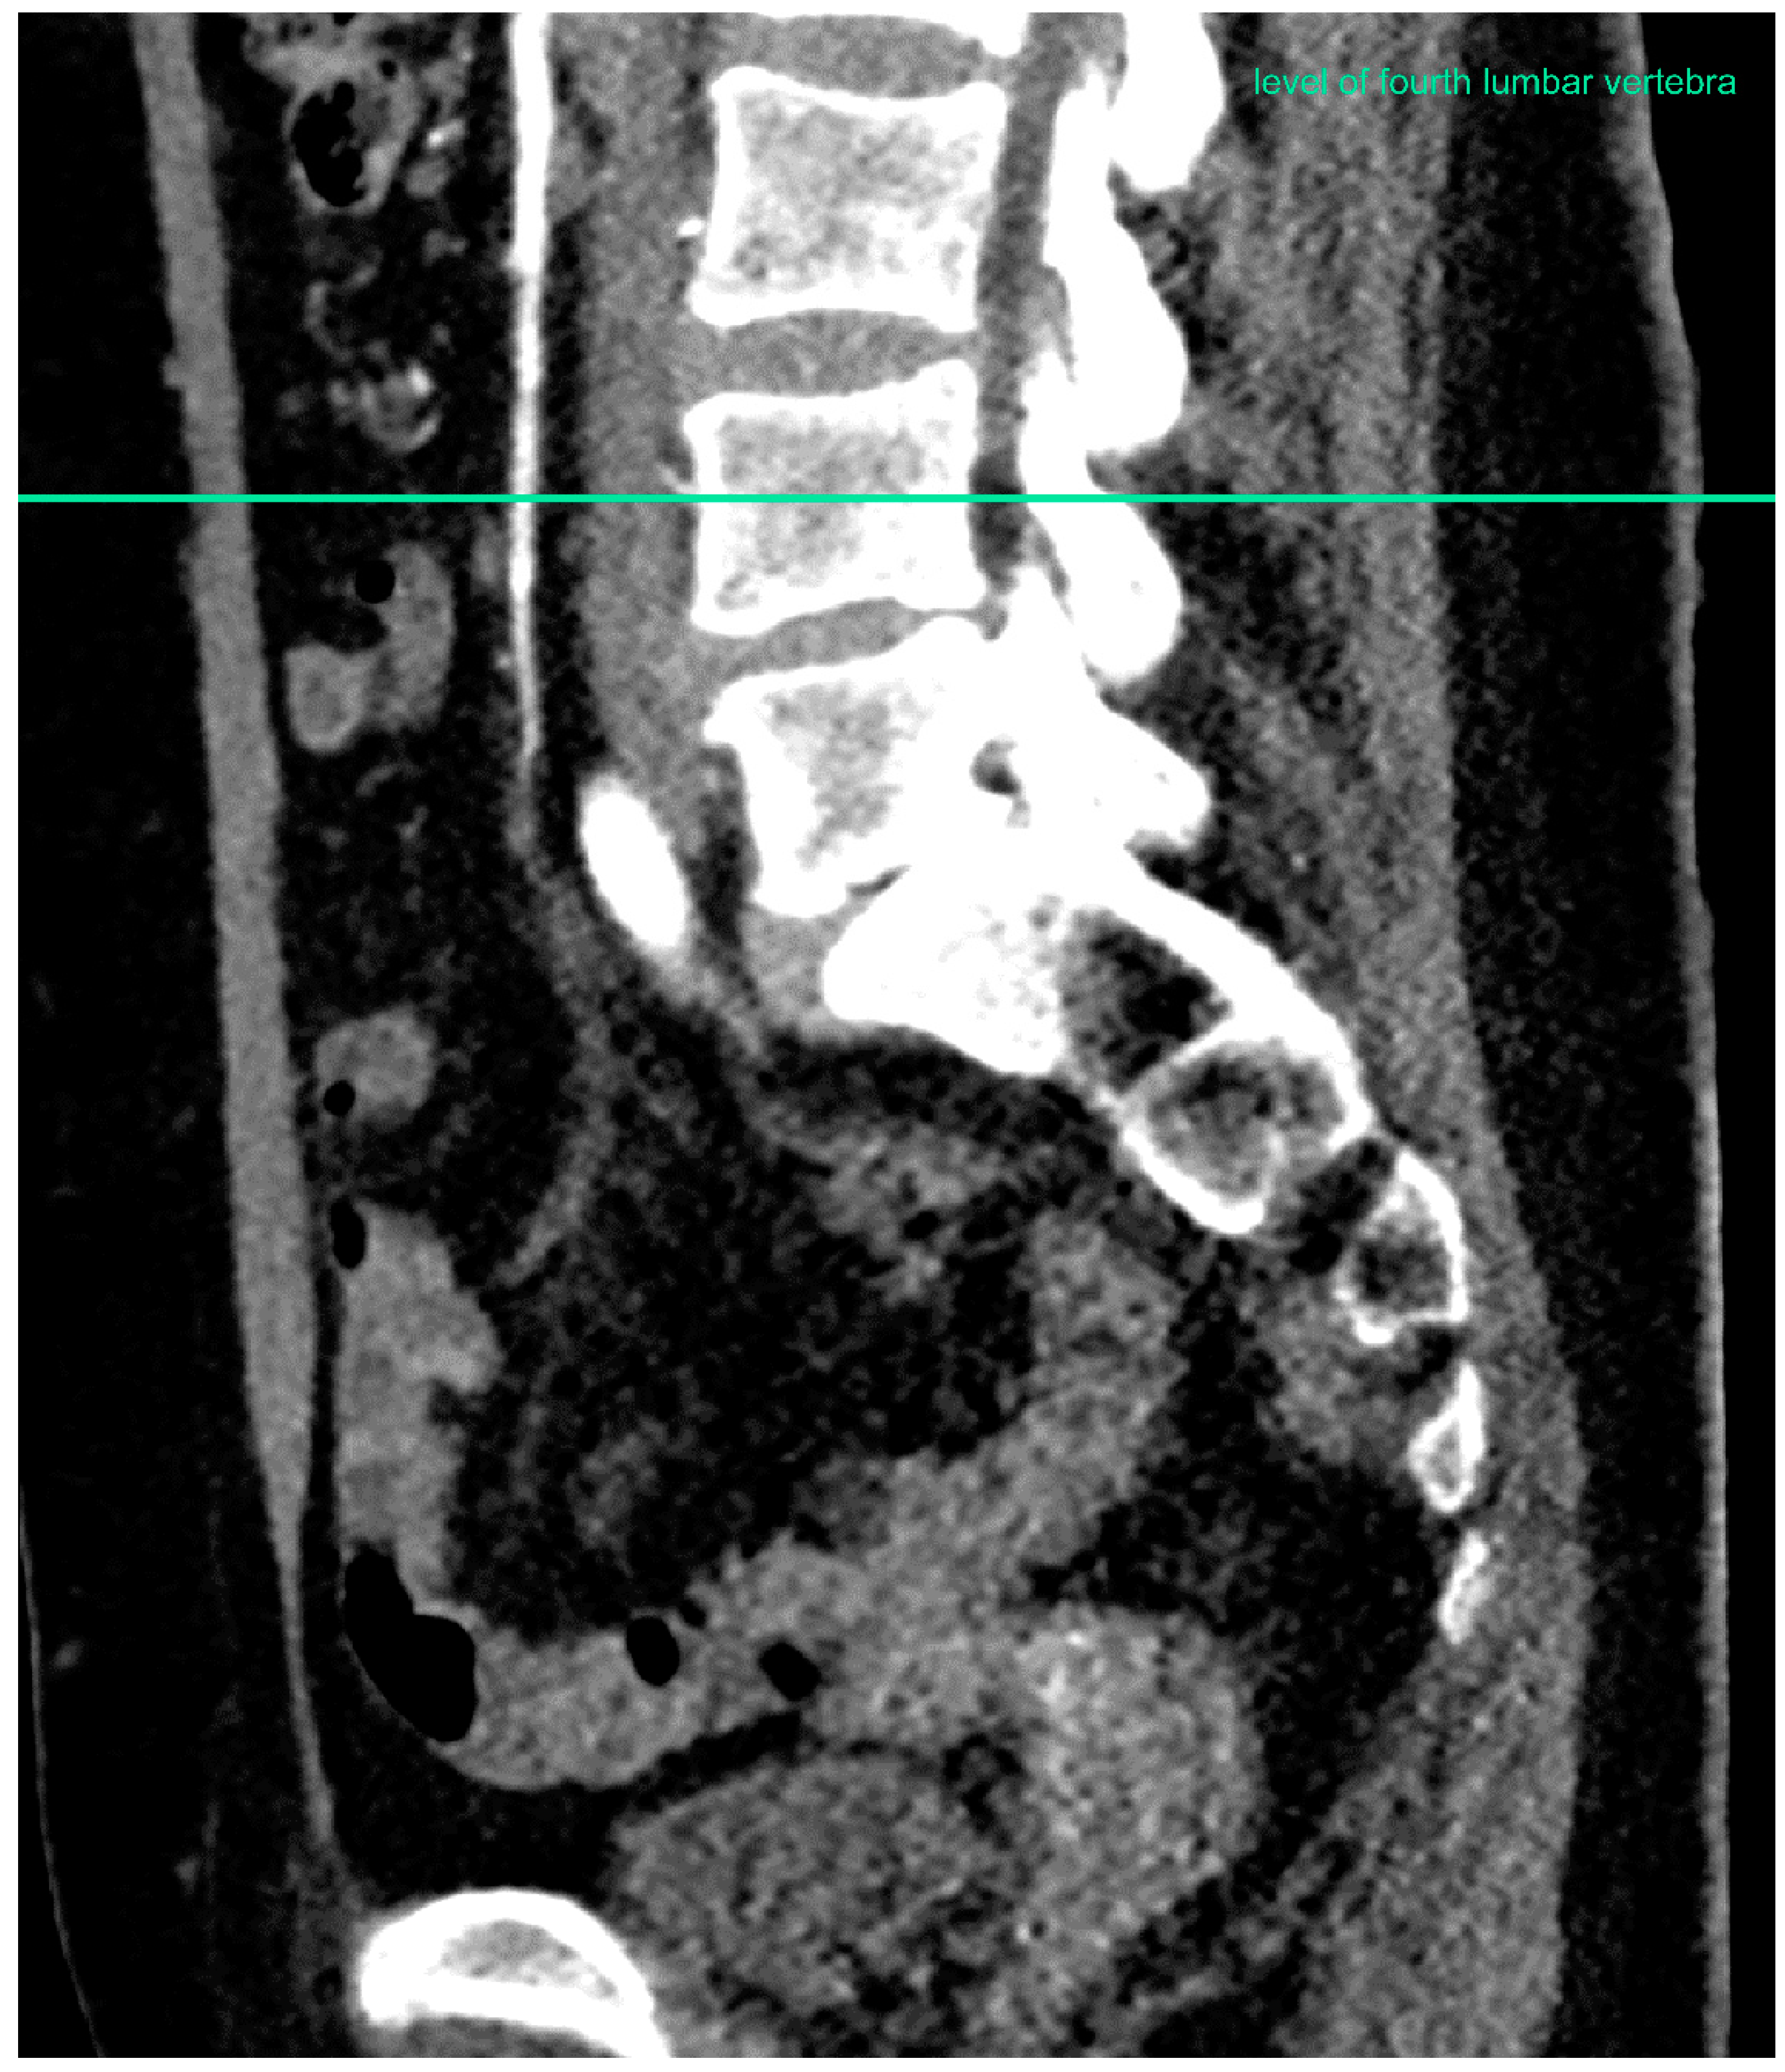

2.2. Computed Tomographic Angiogram Measurements